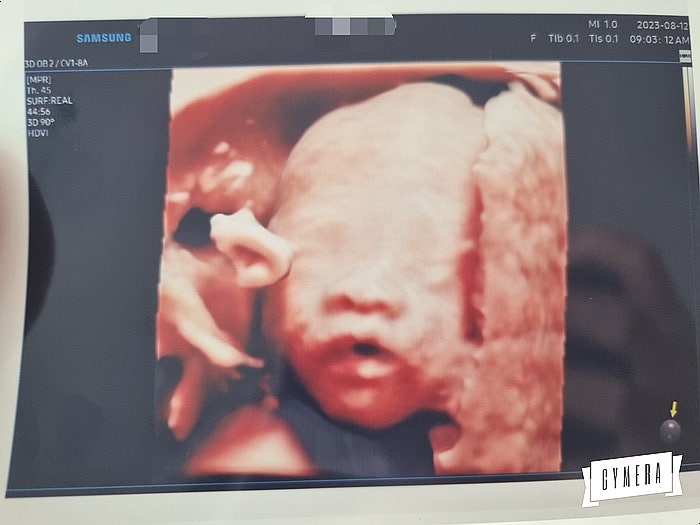

마리아병원 착상 임산부뱃지 임당검사 입체초음파